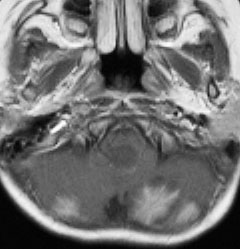

髄芽腫治療後17年目,放射線誘発血管腫からの脳幹部出血

1歳5ヶ月で左小脳半球の髄芽腫になり手術と化学療法して,3歳になってから脳脊髄照射をしました。脳脊髄18グレイ,局所48グレイが入っています。18歳の学生の時のMRIで,左小脳萎縮がありますが普通の生活ができています。

18歳の時に突然,左上下肢の痺れと脱力が生じました。延髄下端から脊髄に小さな出血があります。様子を見ていたら症状はよくなりました。

その後数日の間に,小さな出血を繰り返して,嚥下障害,しゃっくり,頭痛,四肢のしびれなどが出ました。手術をしないで経過を見ました。

7年後のMRIです。延髄脊髄移行部(おそらくC1)に出血痕が残っています。放射線誘発海綿状血管腫といわれるものの画像所見ですが,ほんとのところは静脈閉塞によるうっ血症状と鬱血性の出血といわれています。

症状はすべて良くなりました。今は学校を卒業して,元気に働いています。